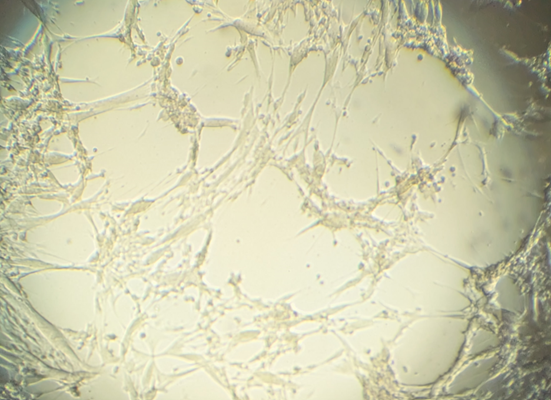

In der Probe wies das LGL BoHV-2 mit sehr hoher Genomlast (Cq-Wert 11) nach (Abbildung 2). Auch unter dem Elektronenmikroskop gelang die Darstellung der Viruspartikel (Abbildung 3). Um im nächsten Schritt festzustellen, ob es sich um infektiöses, vermehrungsfähiges Virus handelt, erfolgte die Anzucht auf KOP-R-Zellen. Bereits nach zwei Tagen waren in der Zellkultur Herpesvirus-typische Veränderungen lichtmikroskopisch zu erkennen (Abbildung 4).

Abbildung 4: Durch Wachstum von BoHV-2 verursachter Herpesvirus-typischer, zytopathogener Effekt auf KOP-R-Zellkultur.